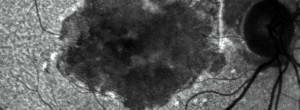

Ensayo clínico OAKS-DERBY: Eficacia y seguridad de pegcetacoplan en el tratamiento de la atrofia geográfica secundaria a DMAE

GALE: seguridad y eficacia a largo plazo del pegcetacoplan en pacientes con AG secundaria a DMAE